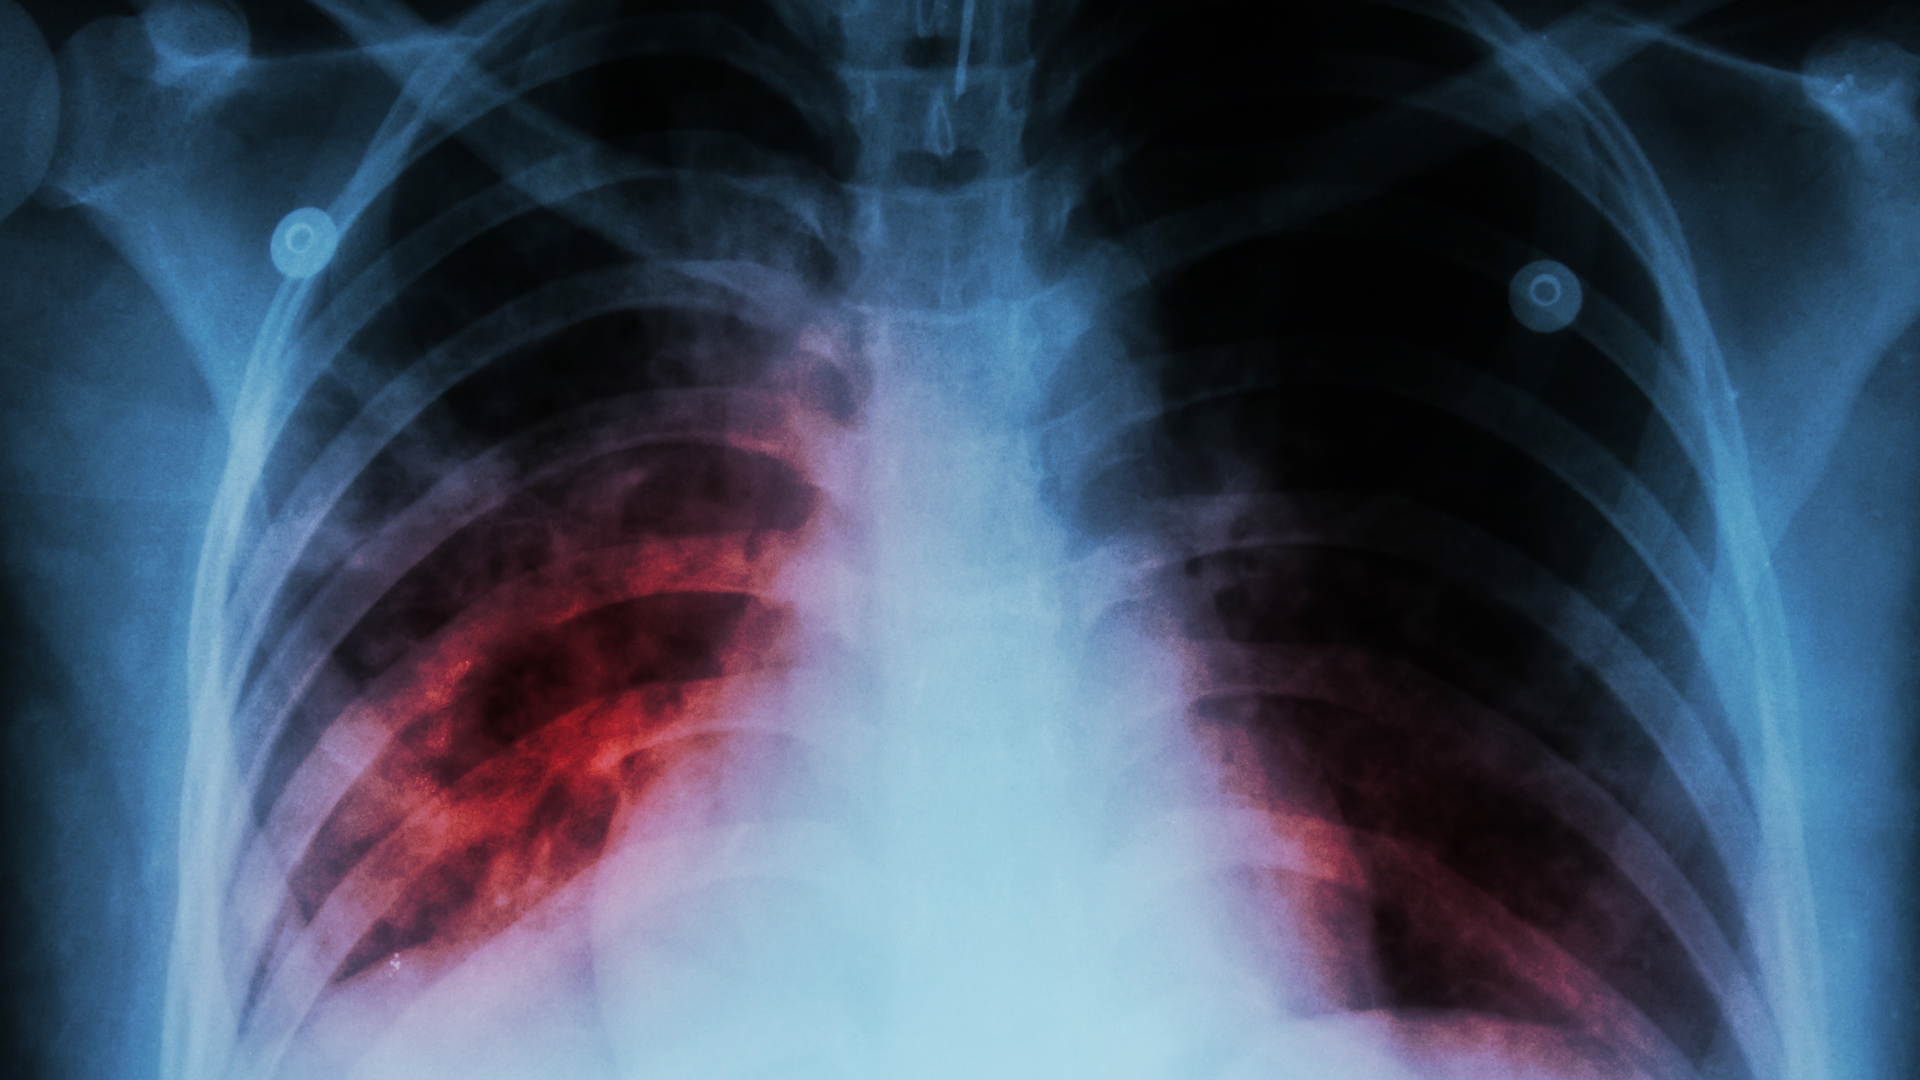

Despite countries making bold commitments to end TB by 2030, in the Sustainable Development Goals, the WHO End TB Strategy, and the 2018 political declaration on the fight against TB, the epidemic shows no sign of slowing down. In 2021, approximately 10.6 million people fell sick with TB, and 1.6 million died. Drug-resistance continues to be a major problem with close to half a million people developing drug-resistant TB every year.

BCG is currently the only licensed TB vaccine. While it provides moderate efficacy in preventing severe forms of TB in infants and young children, it does not adequately protect adolescents and adults, who account for close to 90% of TB transmissions globally.